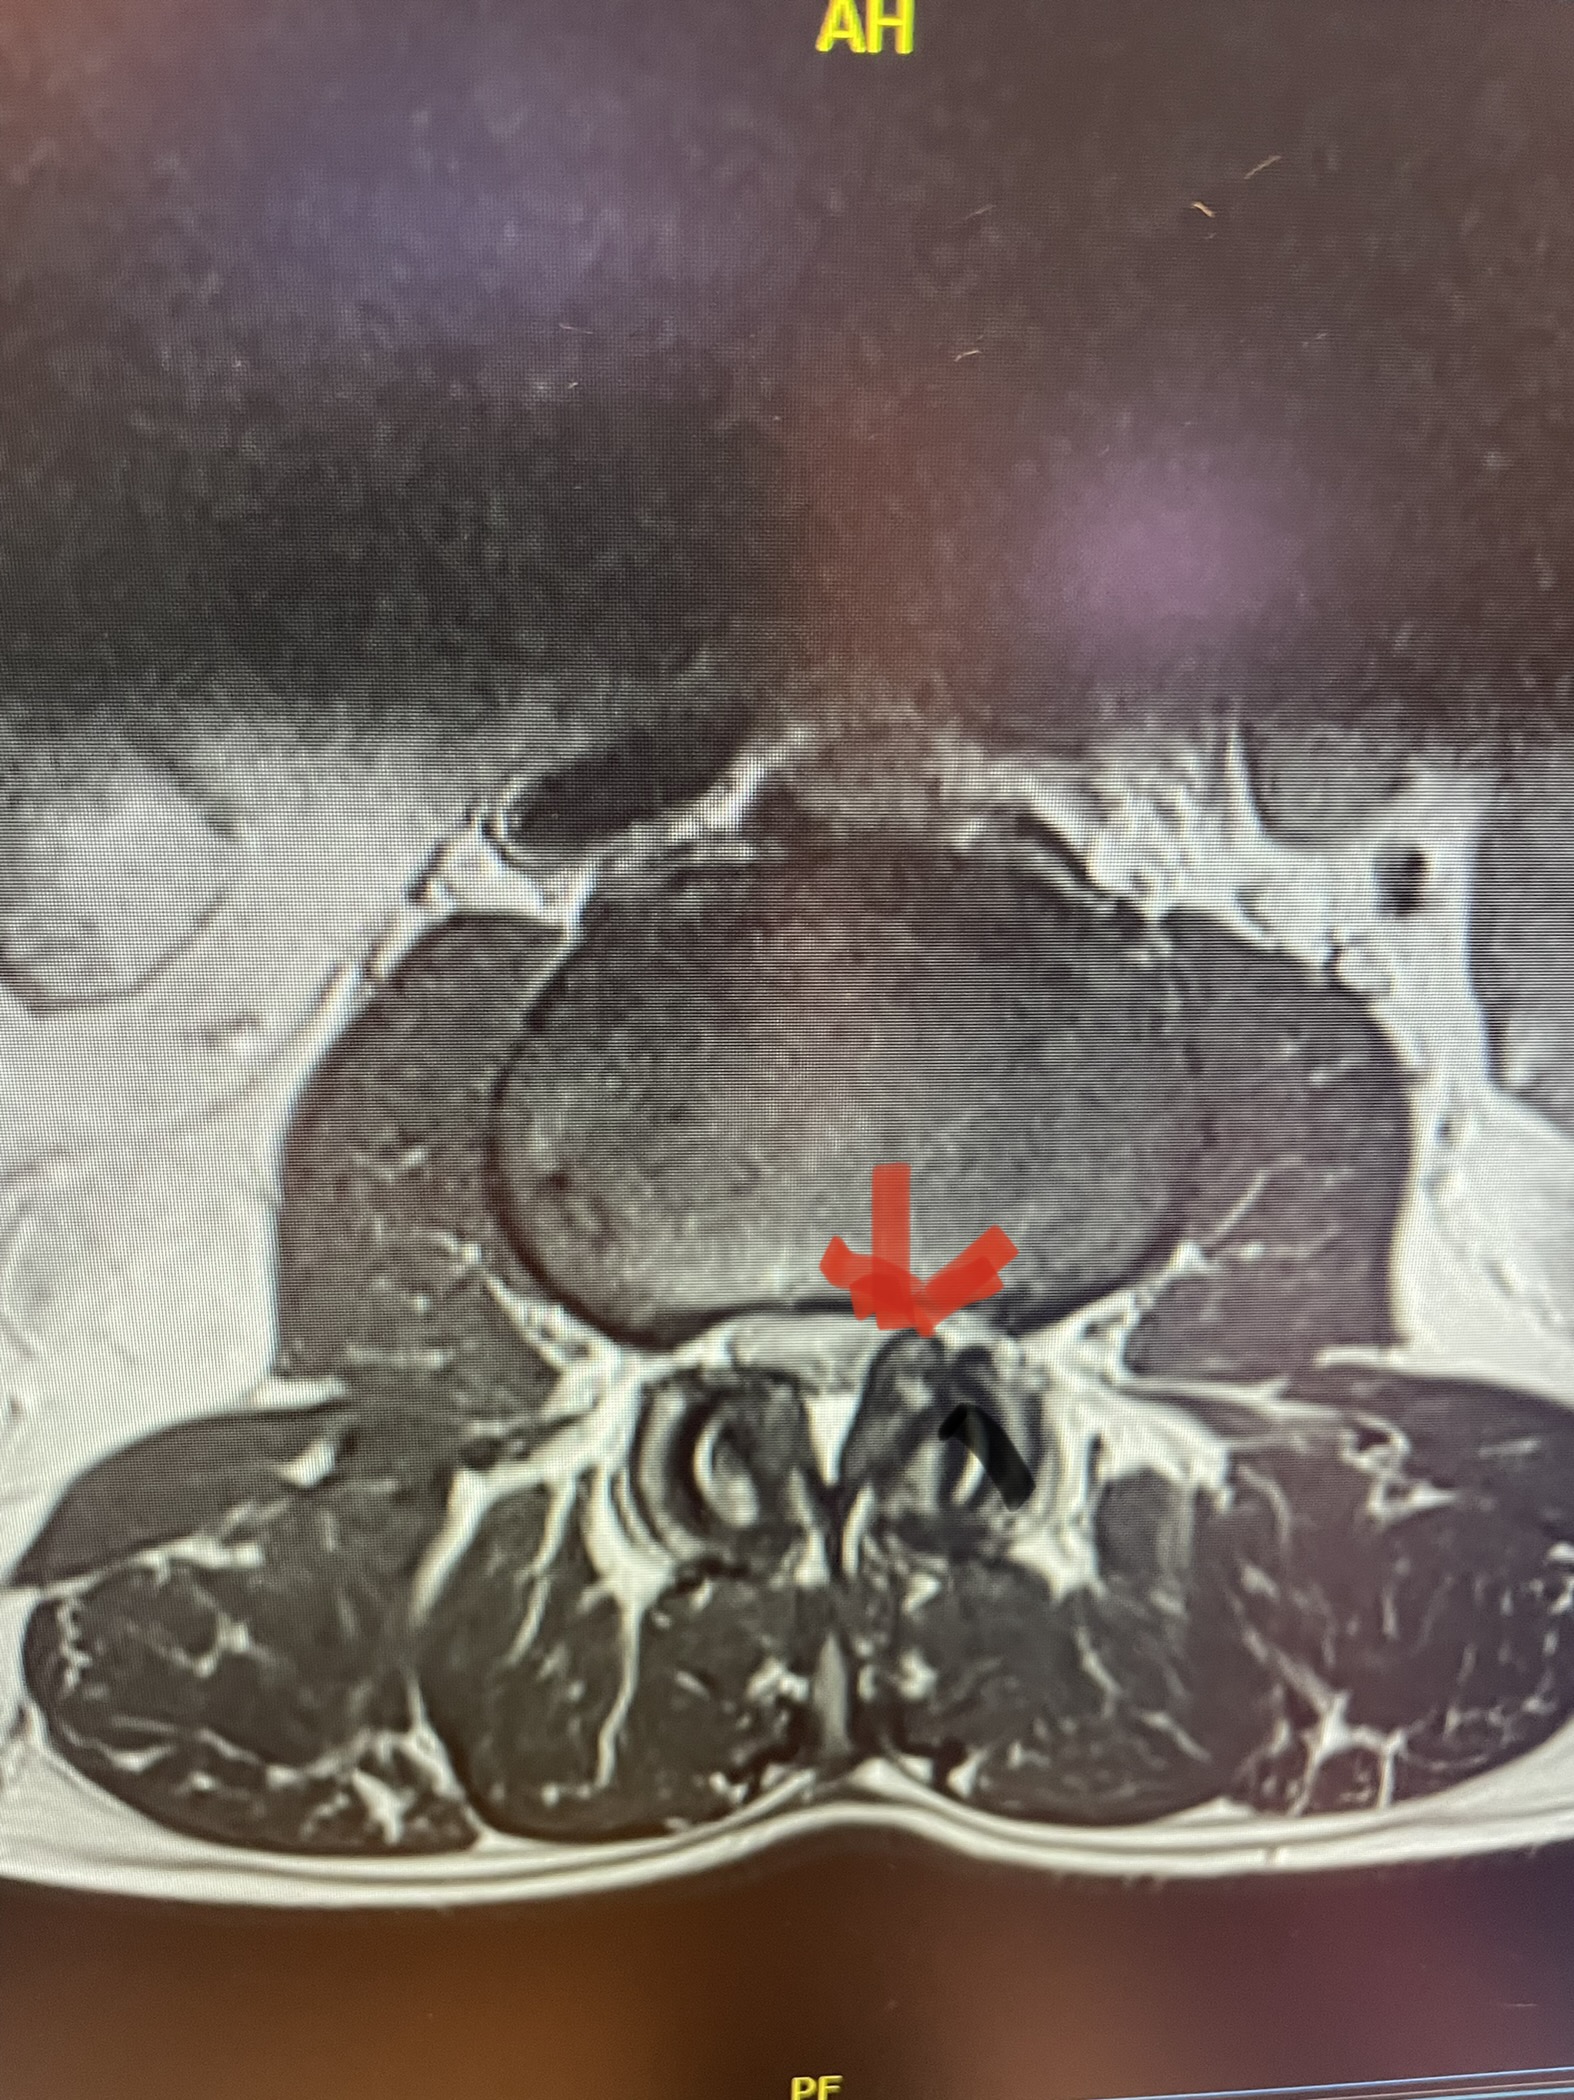

Here is a dramatic example of a patient who had prior laminectomy and fusion surgery four years earlier, and now presents with low back pain with severe burning pain in her right lower extremity pain. She did not respond to epidural steroids. She had a prior L3-S1 laminectomy, and an L3-5 instrumented fusion. A current MRI (Fig 4) demonstrated severe L2-3 next segment stenosis due the development of massively hypertrophied or enlarged L2-3 joint complexes. There was also a grade 1 retrolisthesis of L2 on L3 with a large anterior disc osteophyte complex. The configuration of the stenosis was worse in the right lateral recess secondary to the anterior osteophyte and more right-sided facet compression of the thecal sac, correlating with the patient’s right-sided symptoms. When the anatomy correlates with the patient’s symptoms that is the best set up for success. It was decided to offer a revision surgery to the patient, who agreed.

Fig 4: Sagittal and axial T2-weighted lumbar MRI images demonstrating severe next segment degeneration and stenosis at L2-3 above prior L3-5 fusion. Note retrolisthesis and significant facet arthropathy at L2-3 (red arrow).